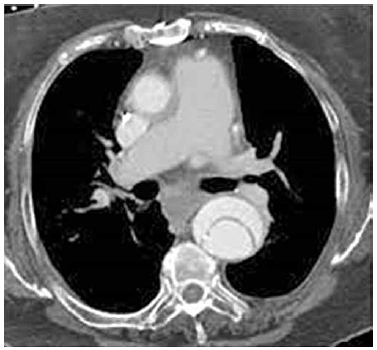

Homem, 60 anos, hipertenso, evolui com dor torácica em dorso de forte intensidade e início súbito, em caráter de facada. Realiza angiotomografia que evidencia a imagem a seguir. Frequência cardíaca de 90 bpm e pressão arterial de 240 x 120 mmHg.

É correto afirmar que